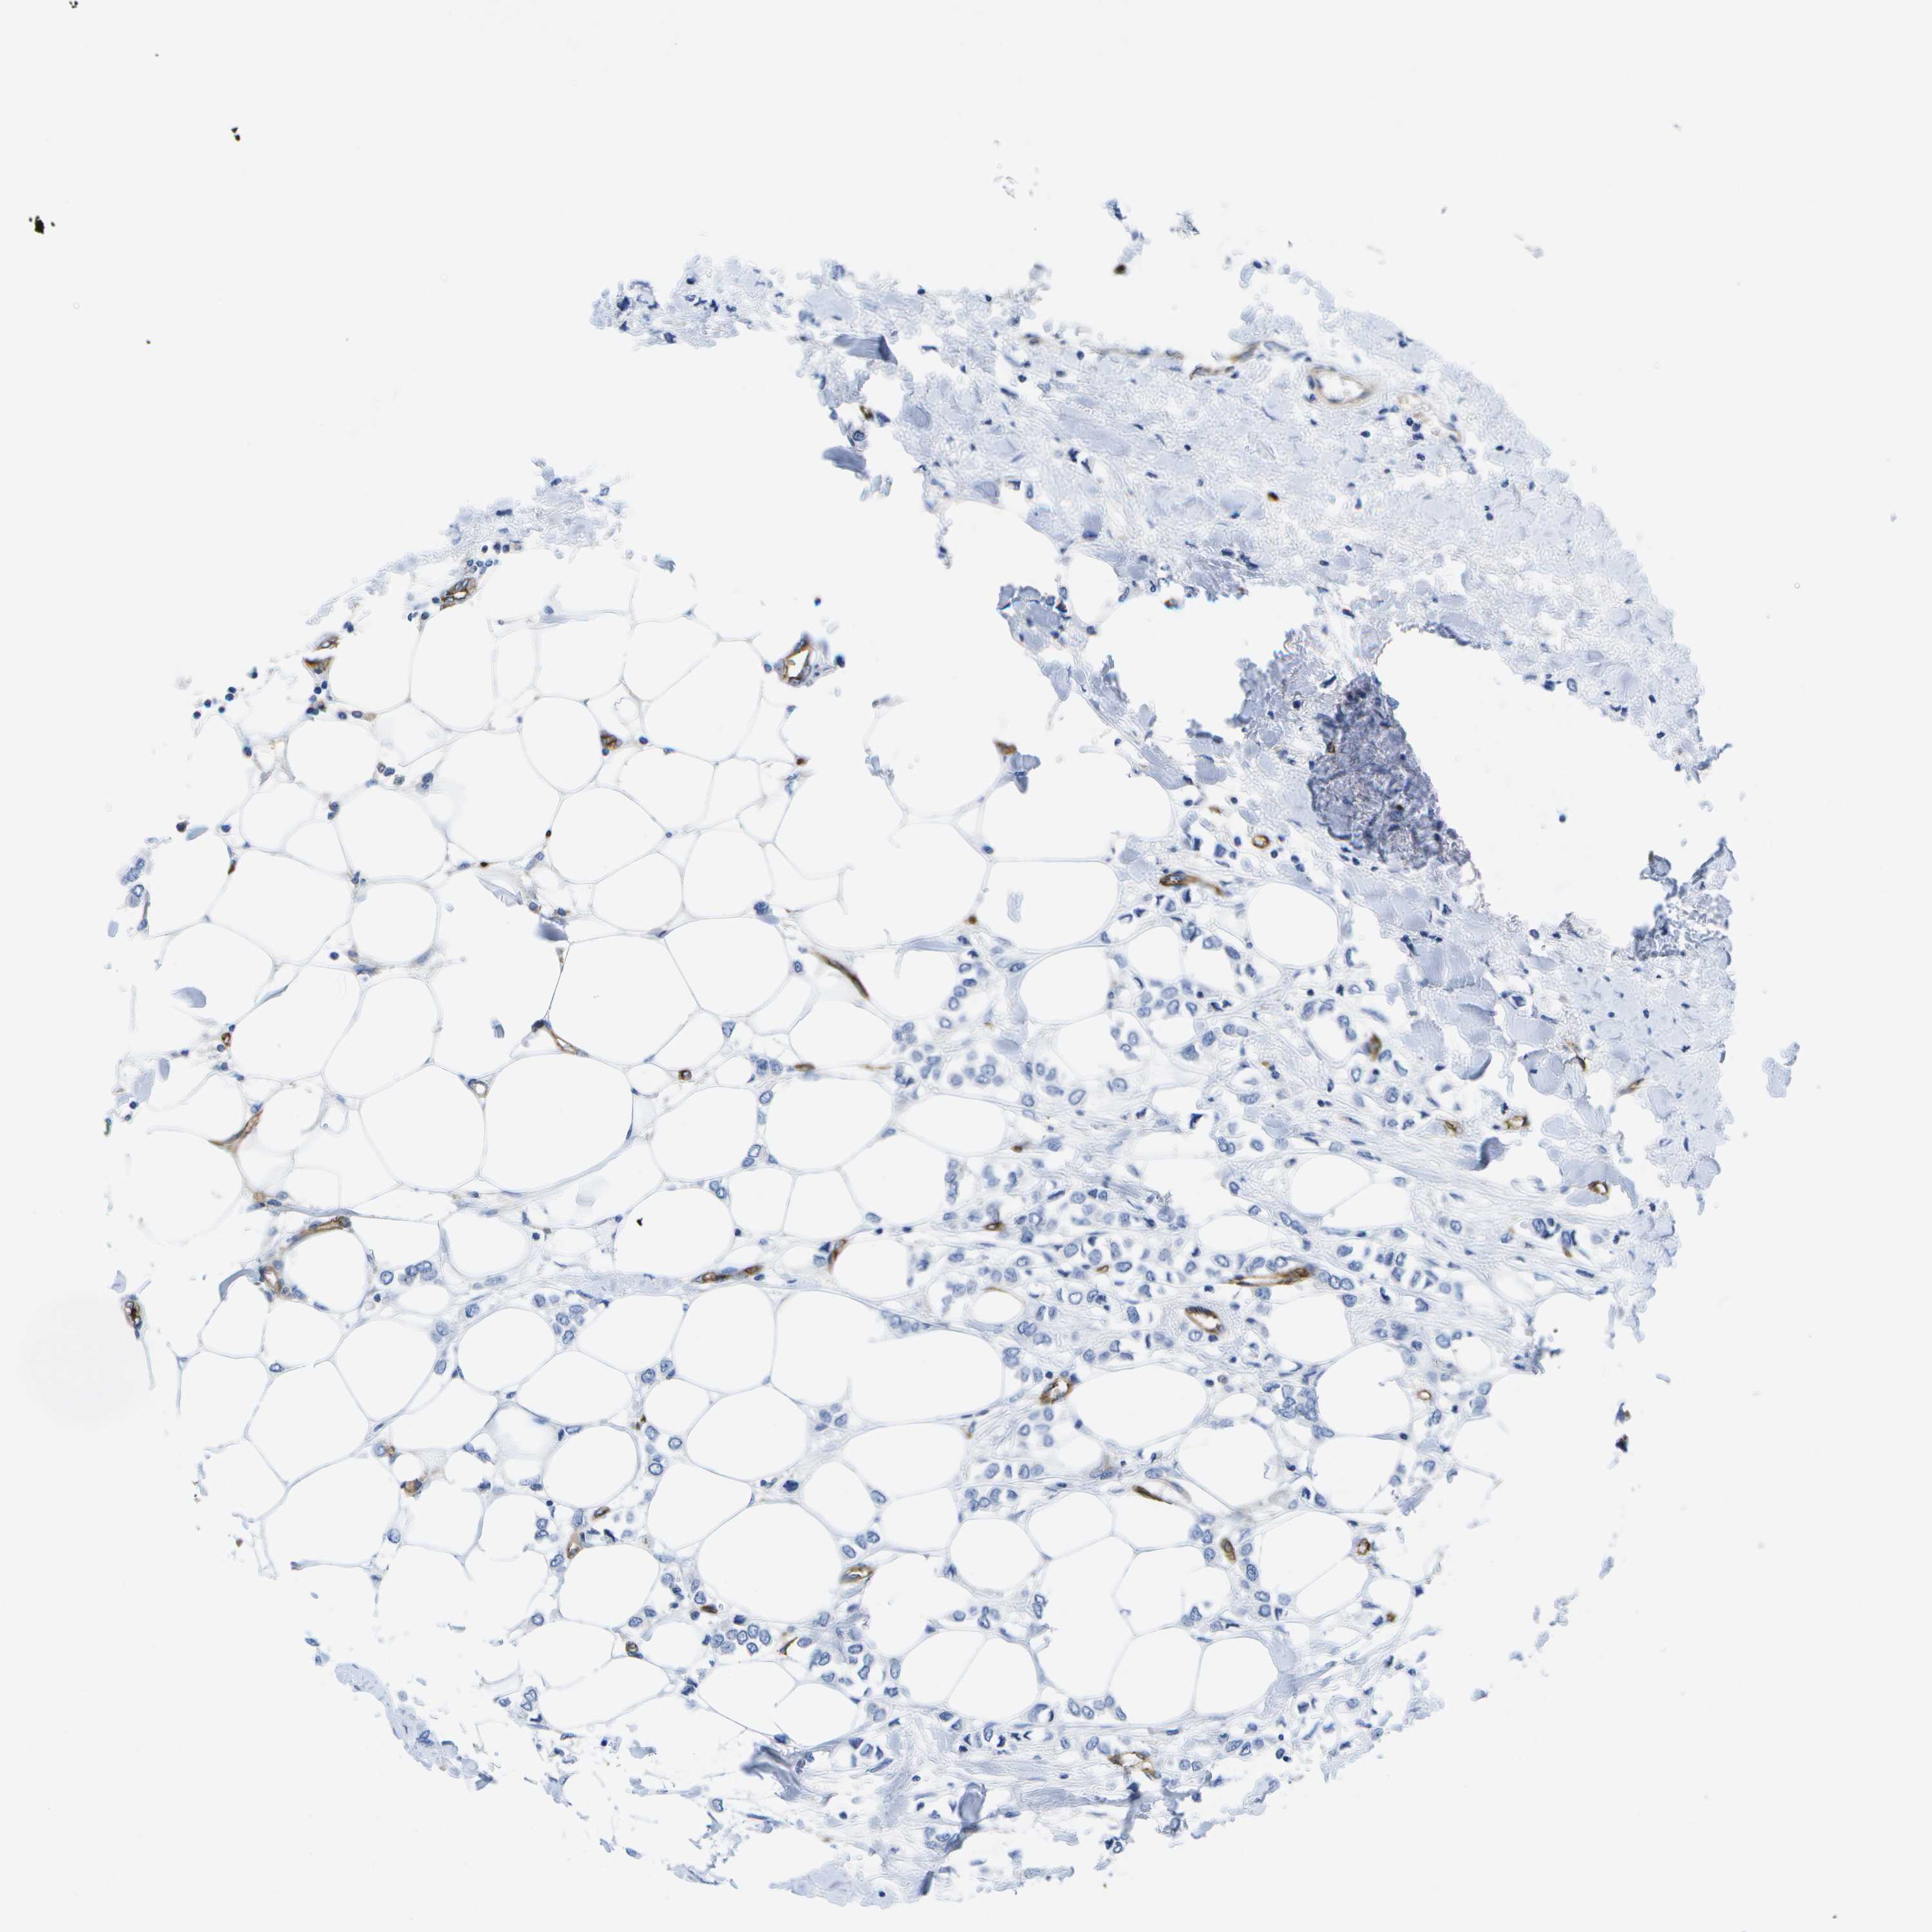

CANCER BREAST CANCER Show tissue menu

BRCA TCGA BRCA VALIDATION PROTEIN EXPRESSION